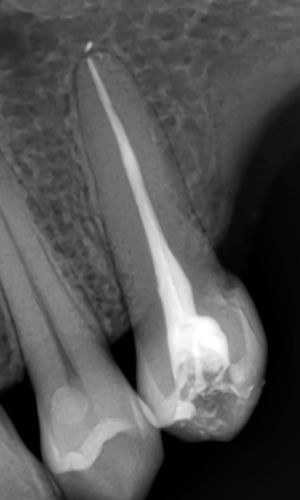

Dental x-rays are typically taken prior to, during, and following root canal therapy and are an essential component of the procedure. The dentist may look inside the tooth’s root canals with the use of these x-rays, which are invisible to the human eye.

An x-ray of a completed root canal treatment. Getty images.